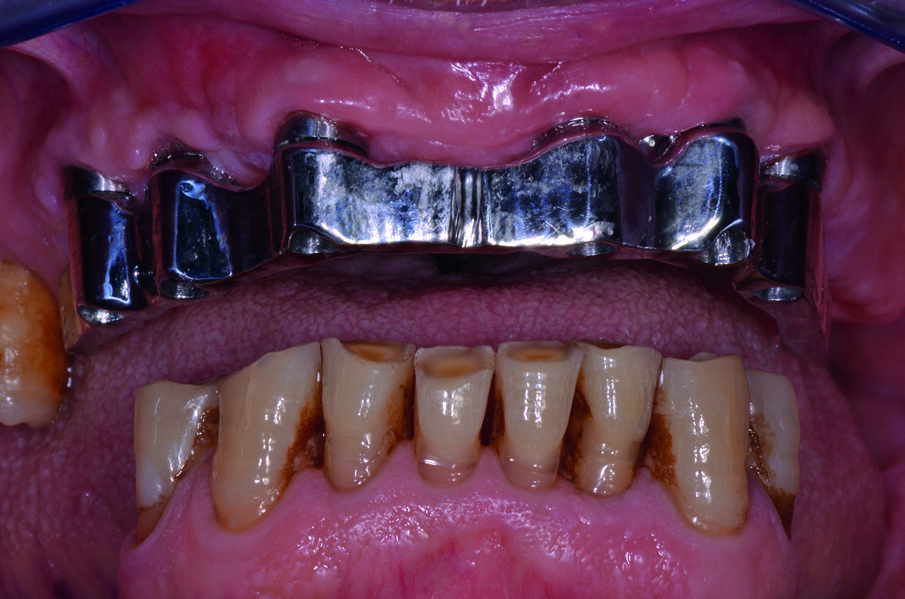

Dopo la terapia chirurgica, si inserisce una protesi totale provvisoria, che il paziente porterà per 6 mesi (Fig. 4b). Dopo i 6 mesi si monta la barra e la protesi totale superiore (Figg. 5, 6), che oltre a migliorare la masticazione e la fonetica del paziente, supporterà anche i tessuti molli, labbro, guancia, ridando al paziente un aspetto del sorriso giovanile e un supporto dei tessuti molli orali delle labbra, delle guance e delle rughe geniene (Figg. 7, 8). Il paziente viene inserito in un piano di mantenimento con un follow-up ogni 3 mesi (Fig. 9).

Per il trattamento di igiene orale domiciliare e professionale è importante prevenire mucosite e perimplantite, Si è rimotivato il paziente a corretti stili di vita di igiene orale secondo l’approccio tailor-made, personalizzato e condiviso con il paziente, sia per l’igiene domiciliare che per la terapia parodontale non chirurgica, implementandola con sedute di fototerapia Bioptron (Zepter).